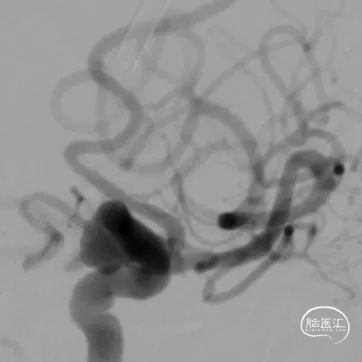

术前DSA、DSA 3D

该病例为右侧后交通段绝对宽颈动脉瘤,动脉瘤体7.2mm*6.7mm*5.7mm,瘤体上多个小子囊,载瘤动脉异常扭曲,直径约4.2mm,工作角度难以选择;另外患者高龄,颈内动脉扭曲且不规则狭窄,因此对支架导管的输送性和支架的贴壁性要求较高。且患者动脉瘤存在多个小子囊,填塞后子囊不显影才能降低再出血风险。手术策略是三导管技术(两根弹簧圈微导管分别放入子囊和大的瘤腔、一根支架导管)。

治疗后工作位减影造影显示动脉瘤致密栓塞,子囊未显影载瘤动脉血流通畅。